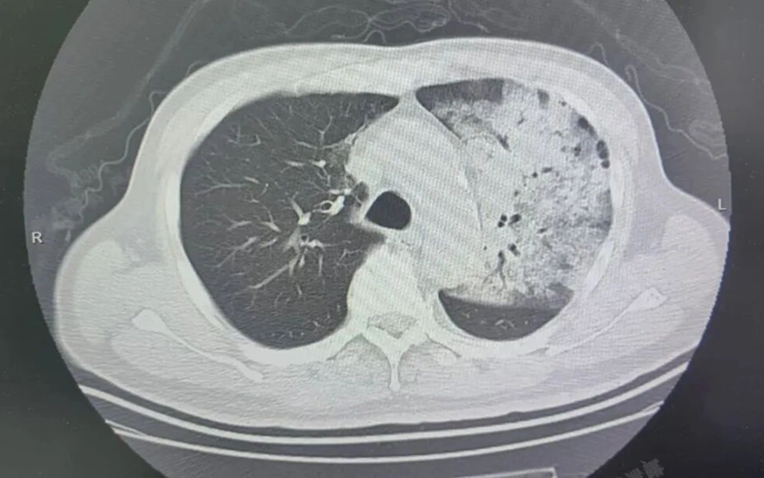

Sau khoảng một tuần điều trị tại bệnh viện địa phương, bệnh tình của ông đột ngột xấu đi. Bệnh nhân bắt đầu khó thở, rối loạn ý thức. K ết quả chụp CT cho thấy 2 phổi bị nhiễm trùng nặng, gần như “trắng xóa” . Dù đã được hỗ trợ thở máy nhưng tình trạng oxy máu vẫn không cải thiện.